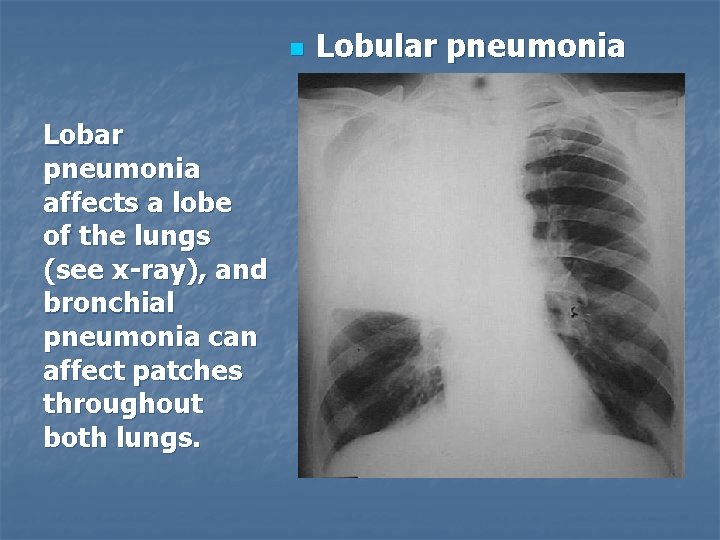

n Lobar pneumonia affects a lobe of the lungs (see x-ray), and bronchial pneumonia can affect patches throughout both lungs. Lobular pneumonia